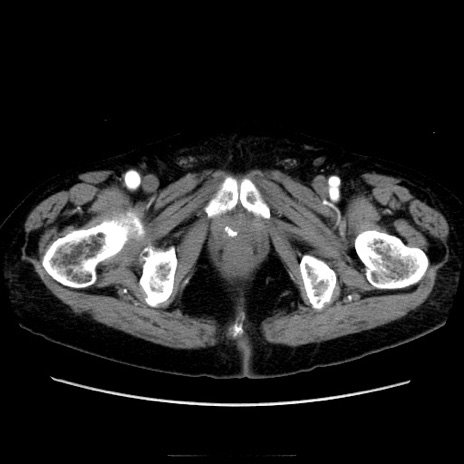

症例21(横断像)

【症例】70歳代男性

【現病歴】肝硬変・肝細胞癌にてかかりつけの方。約9時間前に食後より腹痛出現。症状が徐々に増悪し、嘔吐出現したため来院。

【既往歴】肝硬変、肝細胞癌(RFA、TACE後)